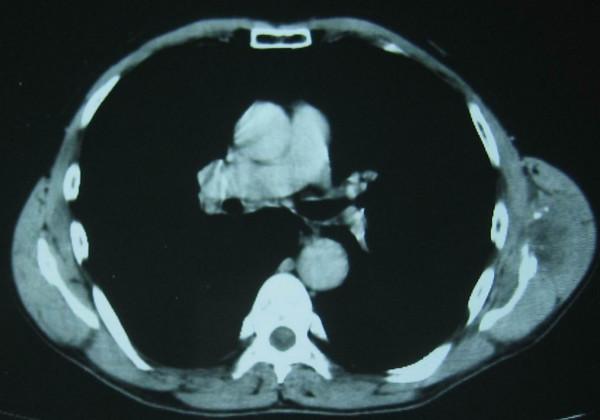

CASE PRESENTATION

We present an unusual case of CCSTA overlying the scapular region and with secondary osseous extension in the lower scapula. The patient underwent a wide local excision with removal of the tumor and the lower two thirds of the scapula. He had no local recurrences but he developed lung metastases after 5 months in spite of postoperative chemotherapy. He finally died ten months later.

病例报告

我们报告一例罕见的CCSTA病例,肿瘤位于肩胛区域并继发于肩胛骨下部骨质浸润。患者接受了广泛的局部切除,切除了肿瘤及肩胛骨下三分之二。患者无局部复发,但尽管术后进行了化疗,5个月后仍出现肺转移。10个月后患者最终死亡。